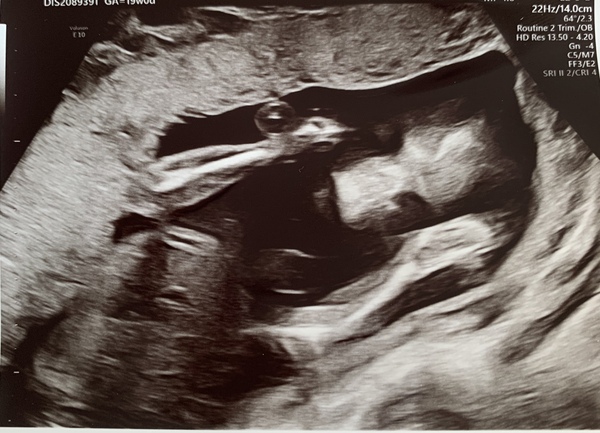

Here are a few photos of our little pickle - I'm obsessed with those little toes x

@danielasummer omg those feet I'm obsessed 👣👣👣

I love seeing my baby sitting down like that as well - even if it is on my bladder - I feel like I need to pee constantly has anyone else had that yet. I was worried I had a urine infection but the Sonographer said it was probably how he was sitting.